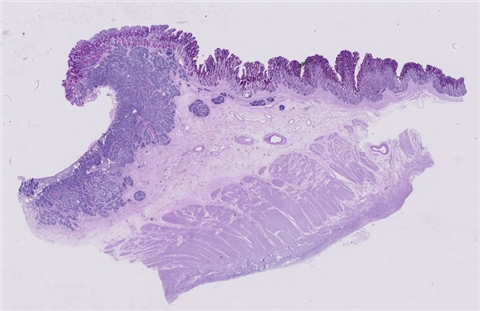

案例9 (6975)

性别:       年龄:41

患者详情: 患者于半年前无明显诱因出现大便带血,为暗红色血便,未见粘液脓血便,反复发作,无腹痛腹胀,伴大便次数增多,并大便不成形,逐渐变细,初未引起重视,亦未行相应治疗,后症状逐渐加重。为进一步诊治,2020年3月入住我院。 直肠指诊:括约肌紧张度:正常,狭窄:无,触痛:无,距离肛门口大约4cm可及一环直肠一周肿块,质硬,移动度差,无压痛,指尖稍可通过肿块,指套染血:有。 电子肠镜示:距肛门4cm直肠处可见一巨大新生物,中间凹陷,底覆污秽苔,环2/3腔生长,钳取6块送病理,余 结肠各段粘膜光整,血管纹理清晰,未见明显的溃疡、息肉。 活检病理示:恶性肿瘤。后行腹腔镜直肠癌根治术。

大体所见: 1、直肠癌肿物:已切开肠管一段,长10cm,一侧切缘周长4cm,另一侧切缘已缝合,长3cm,紧邻缝合切缘见一溃疡型肿物,大小4.5*4*3cm,肿物切面灰白灰黄色、质硬,与周围组织分界欠清,侵及全层。

2、上切缘:灰褐色黏膜组织一块,大小1*1*0.4cm。

3、下切缘:灰褐色黏膜组织一块,大小1.2*1*0.4cm。

免疫组化: 2002032-004#:CgA(弱+)、syn(+)、CD56(+)、 2002032-002#:CK(+)、TTF-1(+)、CD34 +、SMA(-)

医院: 赣南医学院第一附属医院